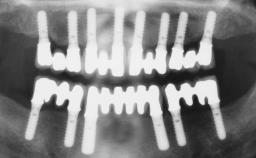

Fixed vs. Removable Prosthodontics for Restoring the Edentulous Maxilla

Fixed and removable prosthodontic implant therapy for restoration of the edentulous maxilla is both complex and challenging. Careful assessment and planning is needed in each individual case to explore whether a fixed or a removable solution will be the more suitable to satisfy the patient’s preference for optimal esthetics, phonetics, comfort and function. This Learning Pathway explores the prosthodontically driven treatment planning based on structured assessment, considered diagnosis and practical application in clinical case examples.